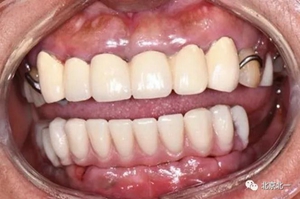

圖十四:口內(nèi)照

圖十九:永久修復(fù)完成

圖二十:永久修復(fù)咬合關(guān)系

圖二十五:口內(nèi)照。